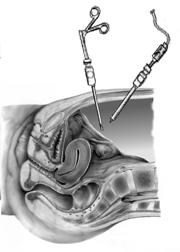

Следующим шагом к преодолению бесплодия с помощью ЭКО явилась встреча в 1968 году Р. Эдвардса с гинекологом Патриком Стептоу и последовавшее за ней 10-летнее сотрудничество в разработке способов забора яйцеклеток с помощью так называемой лапароскопии. Так называют метод визуализации органов брюшной полости с помощью введенного в нее через маленький разрез специального оптического зонда (от греч. lapara — «живот» и scopeo — «смотрю», «наблюдаю»).

Роберт Эдвардс и Патрик Стептоу совершили поистине научный подвиг во имя человечества. 10 лет работы, бесконечные неудачи. Несколько сотен переносов эмбрионов без всякого результата. Это означает, что лапароскопий было сделано еще больше, поскольку далеко не каждая лапароскопия заканчивалась получением яйцеклеток, и далеко не всегда после соединения сперматозоидов с яйцеклеткой наступало ее оплодотворение. Непрекращающаяся критика со стороны коллег. Попытки запретить проведение исследований (как сегодня с клонированием). Первая наступившая беременность оказалась внематочной, вторая прервалась.